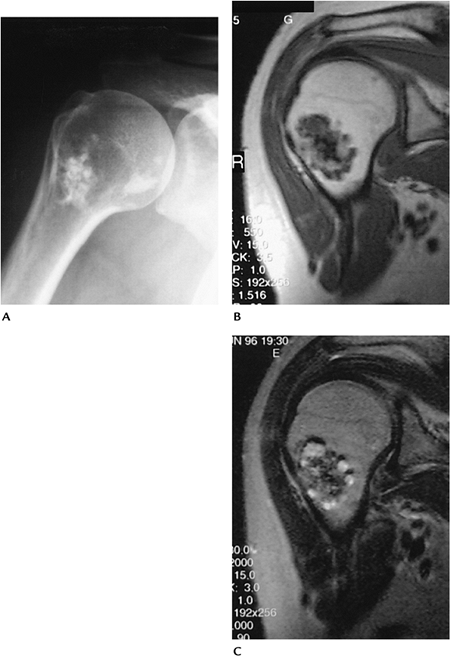

FIGURE 10-14 Enchondroma in a 52-year-old woman. (A)

Routine radiograph of the shoulder showing a focus of calcifications in the marrow of the humeral neck with no endosteal scalloping. Coronal T1-weighted (B) and T2-weighted (C) MR images showing areas of low and high intensity in the enchondroma as the result of calcifications. There is no marrow edema, cortical destruction, or soft tissue mass. |